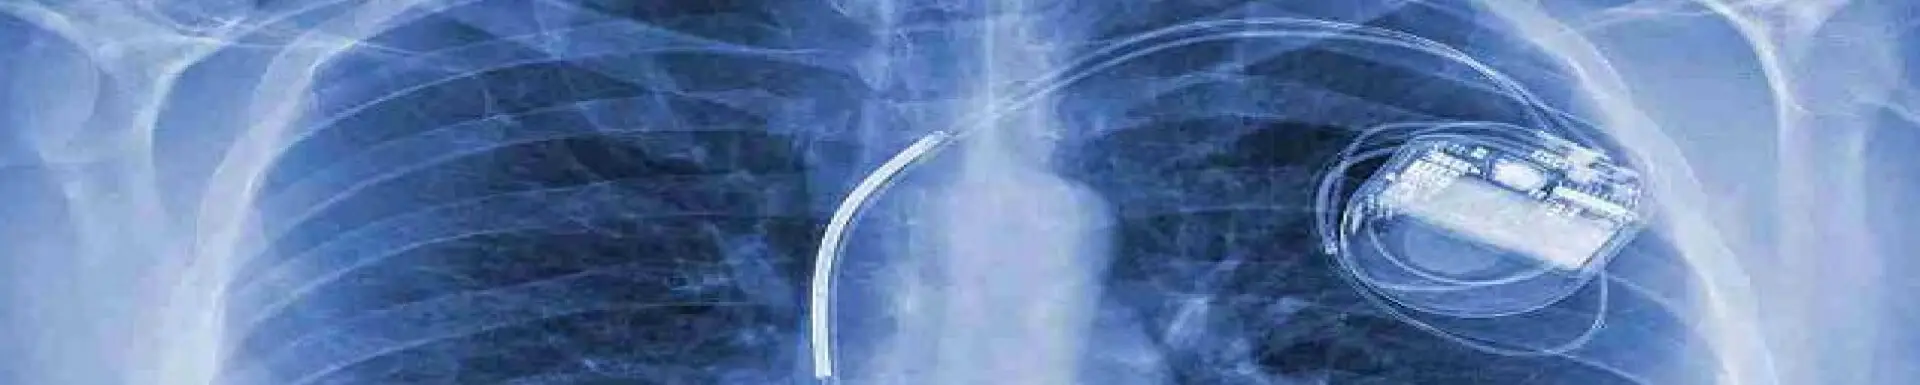

Dexter Magnetic Technologies, an ISO 13485 certified company, is one of the leaders in developing magnetic solutions for implantable medical device applications. Combining an experienced design team with a proven development process, we can assist you in taking your concept to commercial reality. Learn how Dexter’s holistic approach to product development enables us to partner with you to design, test, manufacture, and verify magnetic assemblies for implantable systems.

Miniaturization plays a crucial role in medical devices, reducing the invasiveness of surgeries, and optimizing patient experiences.

By employing bio-compatible materials and coatings, our medical magnets are engineered to be compatible with the human body.